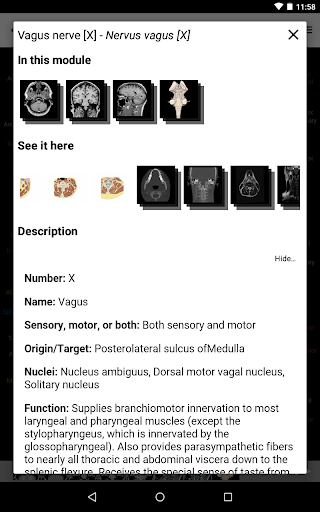

* تحسين عرض التفاصيل للأجزاء التشريحية لتسهيل التعرف عليها في صور الوحدات الحالية والوحدات الأخرى.

- يتم الآن عرض المصطلحات المتعلقة بالهيكل التشريحي في عرض التفاصيل - تمت إضافة